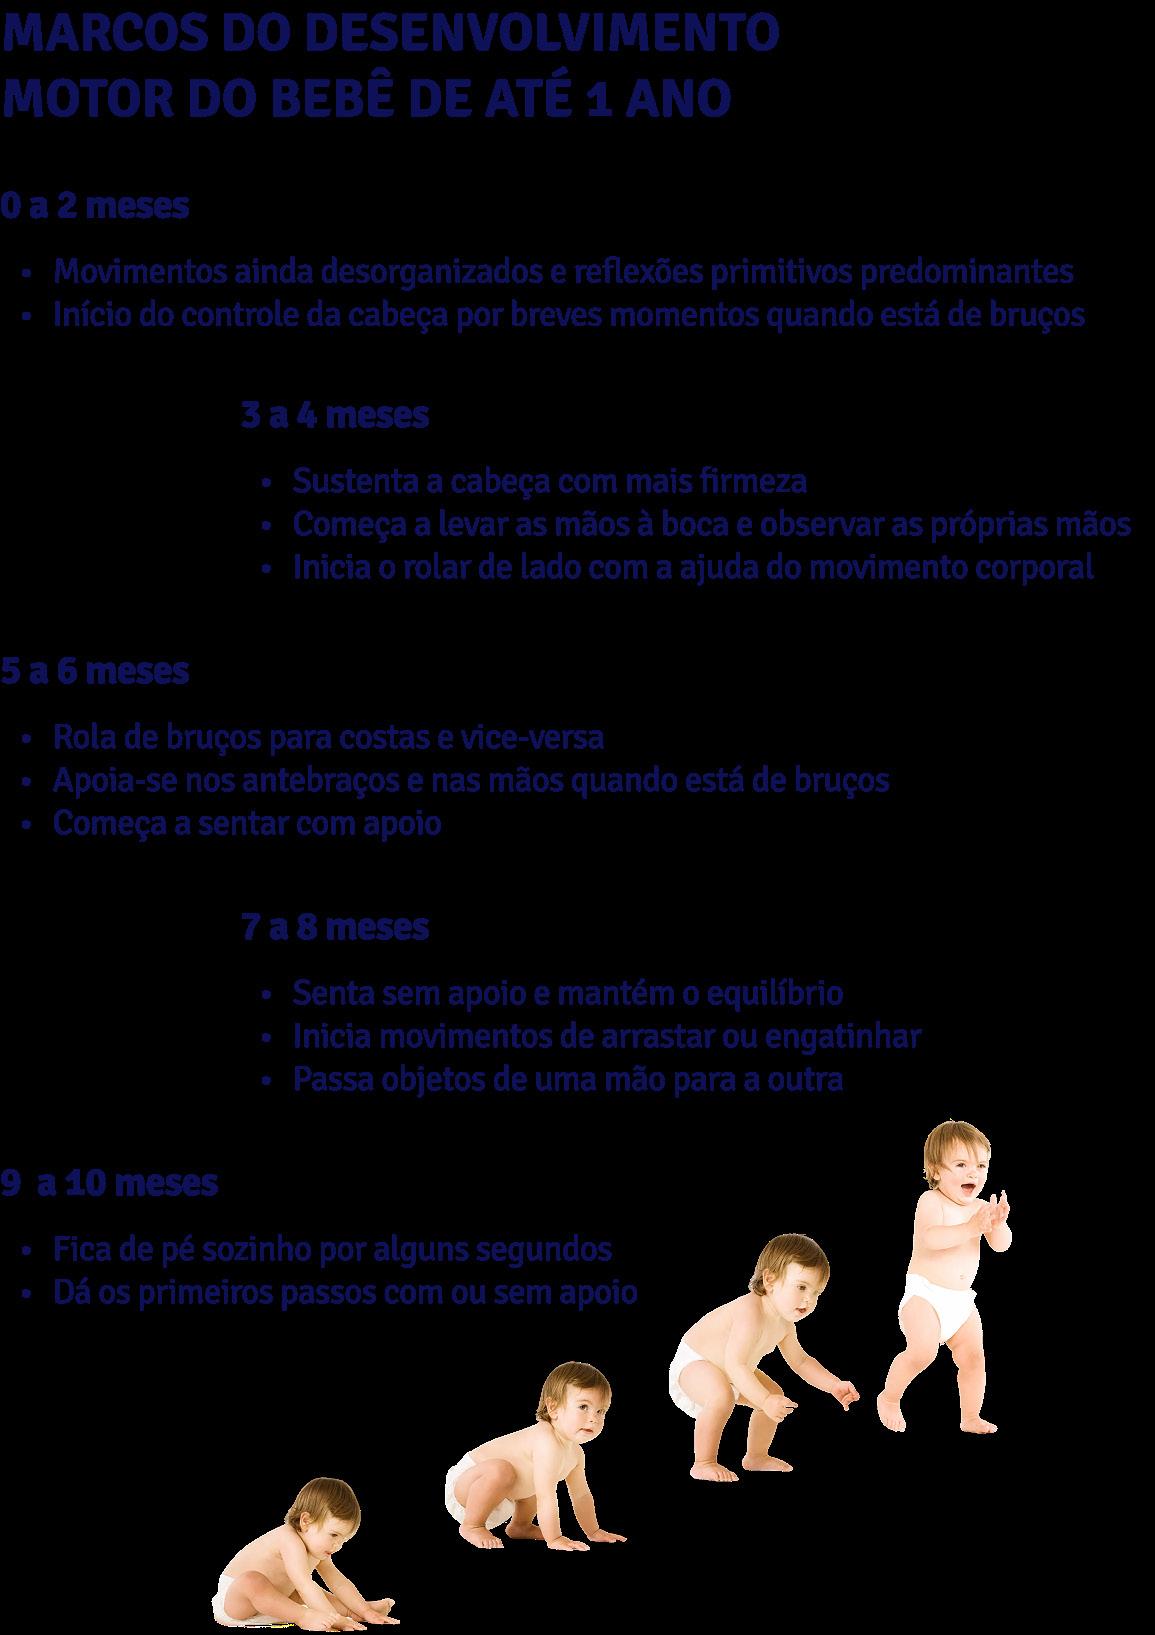

A aquisição de habilidades motoras grossas, também sofre consequências pelo nascimento prematuro, como rolar, sentar-se, engatinhar e andar, em função da imaturidade neurológica e muscular característica desse grupo. Apesar disso, com o avanço do desenvolvimento e o estímulo adequado, as crianças conseguem alcançar essas etapas, ainda que em um ritmo um pouco mais lento quando comparadas às crianças nascidas a termo. Esse acompanhamento deve considerar a idade corrigida e incluir oportunidades de movimentação e interação sensorial que favoreçam o ganho progressivo de força, equilíbrio e coordenação,

além do uso de brincadeiras e estímulos no dia a dia hospitalar e domiciliar (Chorna et al., 2017).

Nesse sentido, a avaliação do bebê e da criança com histórico de prematuridade deve considerar não apenas os marcos motores cronológicos, mas o contexto, o ambiente e a qualidade do movimento. É fundamental utilizar instrumentos validados e respeitar a idade corrigida até os dois anos de vida.

Silva et al. (2024) apresenta autores que destacam a importância fundamental de uma observação cuidadosa das conquistas motoras nos primeiros meses de vida dos bebês prematuros, justamente por ser um período crucial para o desenvolvimento neuromotor e para marcar sinais de alerta para atrasos. A sustentação da cabeça, a manipulação de objetos, o controle dos movimentos dos membros e a aquisição de padrões posturais adequados devem ser acompanhados de forma sistemática. A detecção precoce de qualquer alteração permite intervenções direcionadas, favorecendo o fortalecimento muscular, o alinhamento postural e a promoção de experiências motoras que contribuam para o desenvolvimento global do bebê.

Outros estudos mostram que a evolução das posturas motoras (posturas mais baixas como controlar a cabeça, sentar-se sem apoio e engatinhar), deambular com e sem apoio, são desenvolvidas com satisfação em crianças que recebem intervenções precoces, com programas estruturados desde o nascimento. Esse desenvolvimento pode ser visto, inclusive, em crianças com deficiências neurológicas que são atendidas precocemente, mesmo que em tempo mais prolongado de intervenções (VAN GORP et al., 2018).